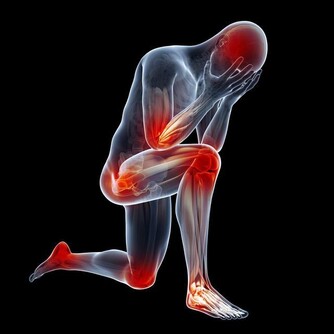

下肢青筋——靜脈曲張 小腿有青筋,即我們所說的下肢靜脈曲張,需要長時間站立或體力勞動較重的人容易出現這種情況,開始往往沒有任何疼痛症狀出現,但可以見到青筋,需要引起重視。常見不適表現為疼痛,嚴重者會出現下肢腫脹、潰瘍、出血等症狀。 調理方法:1.如果在治療時只是輕度的疼痛,可以適當地使用紅花、艾葉泡腳,緩解疼痛症狀。2.若出現嚴重的疼痛則需要及時到醫院綜合治療,採用血府逐淤湯、桃紅四物湯等中藥都可以很好地活血化淤止痛。